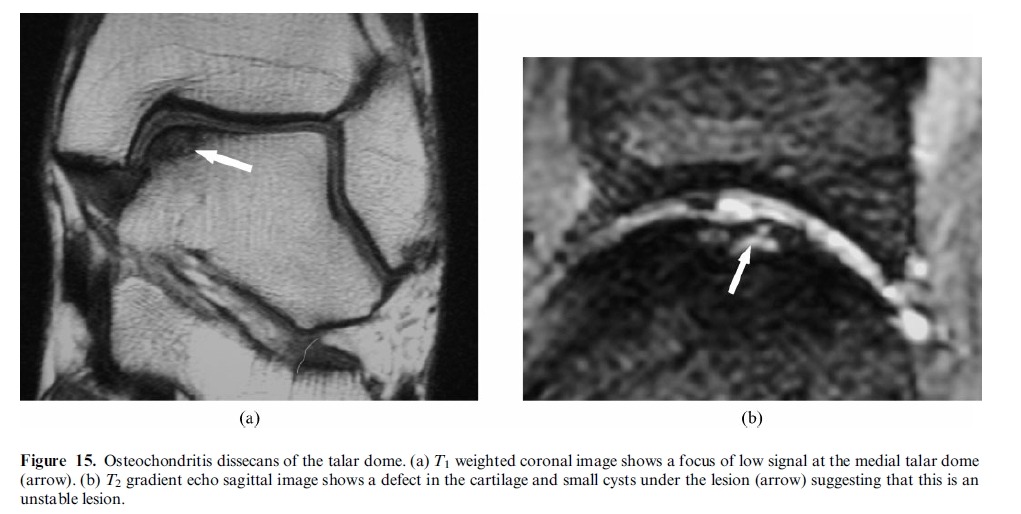

Subtle osteochondral fracture of the lateral corner of the talar dome